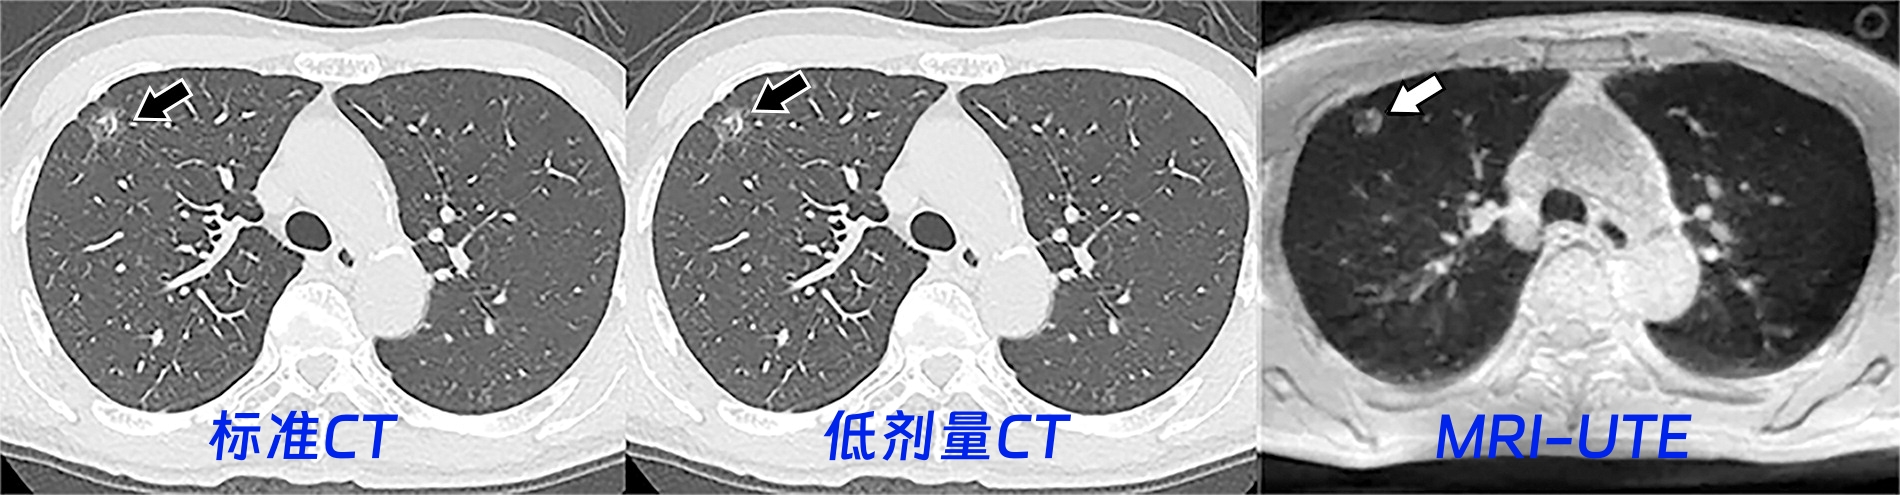

下图展示了一个65岁男性的三种肺部影像。该结节如箭头所指,被诊断为部分实性结节;Lung-RADS分类为3类。

6580a0c7d3a4feb17d4ee45fc465b870.jpeg